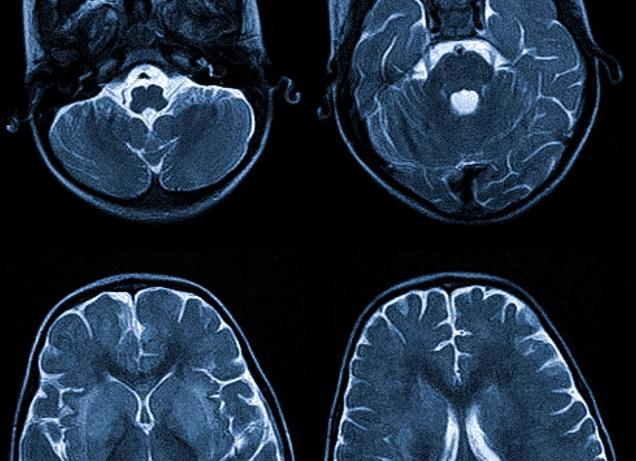

МРТ головного мозга представляет собой инновационный вид обследования, в ходе которого получают снимки тканей и органов в разных ракурсах.

Снимки МРТ

Изучая полученные данные, врач может выявить наличие:

- Патологических воспалительных процессов.

- Негативных изменений в тканях.

- Развитие опухолей.

- снимок мозга Магнитно-резонансная томография — мигрень видно по наличию очагов множественного ишемического генеза, белого вещества лобной доли. Во время ослабления приступа наблюдаются изменения кровотока. Признаки мигрени на магнитно-резонансном томографе связаны с этиологией неврологического нарушения. Непосредственно перед приступом сосуды головы расширяются и затем резко сужаются. Такие изменения можно легко обнаружить, проведя диагностику во время обострения и сразу после него.

После магнитно-резонансной томографии диагност получает серию пошаговых срезов с изображением зоны интереса. На основании снимков можно оценить состояние органов, выявить патологические изменения в тканях, воспалительные и опухолевидные процессы.